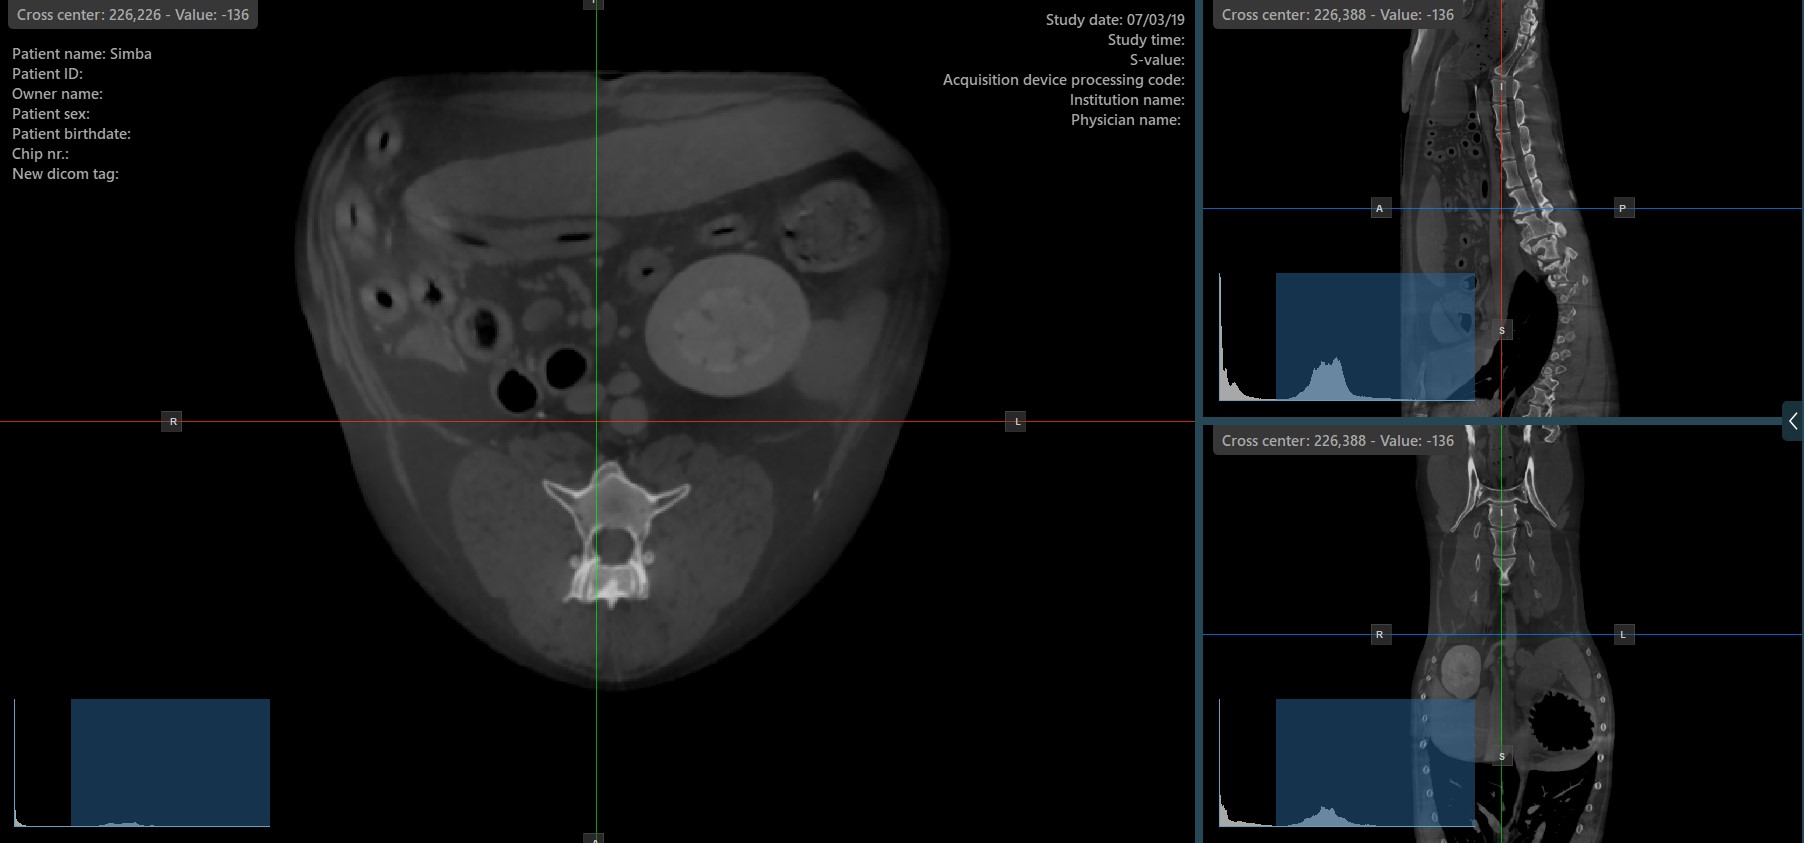

Change Slicers Cross Center Position¶

Altering the position of the cross center of slicers will change the position of the corresponding two image planes. The cross center of the slicers can be selected by using the Select Item (Default) tool, assigned to the right mouse

button by default.

Once selected, drag the cross center of the specific slicers to the desired direction to move its position. The corresponding image planes’ orientation changes accordingly.